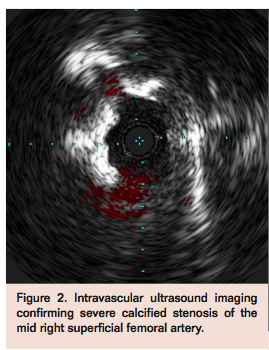

Access was obtained in the left common femoral artery (CFA) and a 7 Fr Pinnacle Destination sheath (Terumo) was positioned across the aortic bifurcation in the right CFA. Selective angiogram of the right lower extremity confirmed mid to distal 80% calcified stenosis of the right SFA (Figure 1), mild popliteal artery disease, and 2-vessel run-off into the right foot. A Grand Slam Wire (Abbott Vascular) was advanced across the right SFA lesion into the distal peroneal artery after anticoagulation with intravenous heparin. Intravascular ultrasound (IVUS) imaging (Volcano) was performed to determine the burden and character of the plaque, which confirmed a severe calcific and eccentric stenosis in the mid SFA (Figure 2). Rotational atherectomy with aspiration thrombectomy was performed using a Jetstream 2.1/3.0 atherectomy catheter (Bayer HealthCare) with four passes across the lesion, two with blades down and two with blades up (Figure 3). Follow-up angiography displayed improved flow but with a non-flow-limiting dissection within the treated segment of the right SFA (Figure 4). Repeat IVUS imaging confirmed an intimal flap consistent with post-atherectomy dissection (Figure 5). Nitinol-constrained balloon angioplasty was performed using a 5 mm x 80 mm over-the-wire Chocolate PTA balloon catheter (TriReme Medical) with a prolonged expansion over 2 minutes (Figure 6). Final angiogram demonstrated excellent angiographic result with brisk flow through the treated segment (Figure 7) and preserved run-off into the foot. Final IVUS imaging confirmed no residual dissection flap and improved luminal gain (Figure 8).